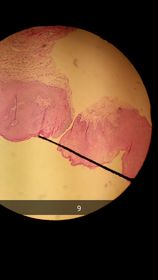

Encía: Plano Estratificado no queratinizado